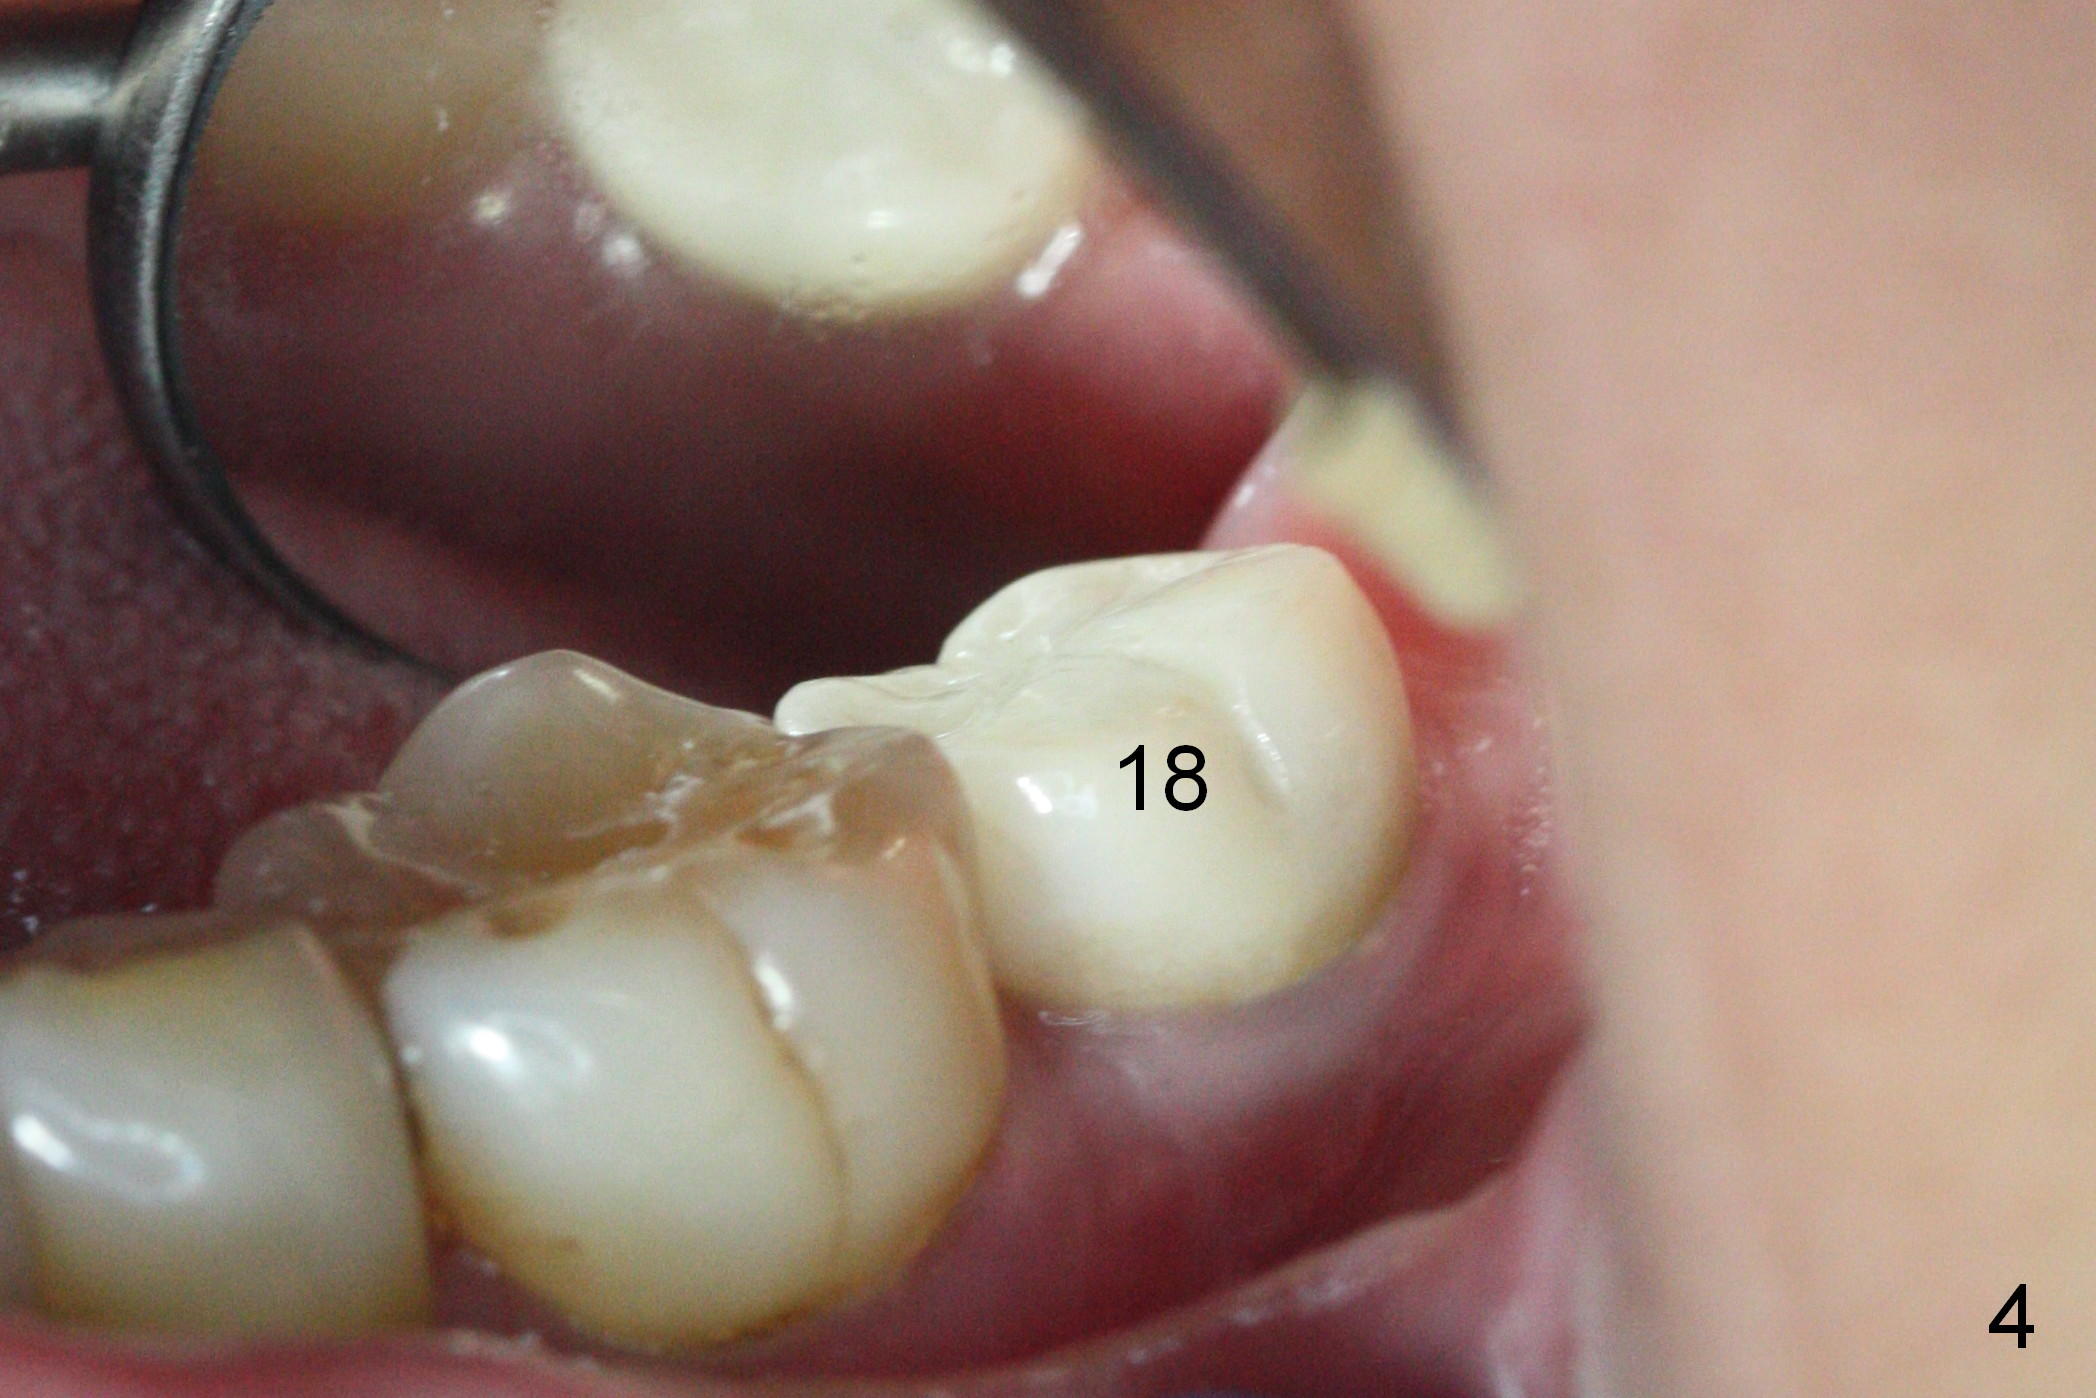

A 65-year-old woman was pleased with functionality of the implant crown at #18 immediately post cementation (Fig.1 (taken 6 months post cementation).  In 2 years and 8 months, she complains of gingival irritation after food impaction.  Although the proximal contact is slightly light with floss, the gingival embrasure feels to be extremely large (Fig.1 *).  When the crown is to be remade, increase the vertical contact (Fig.2 red line) to close the gingival embrasure as much as possible.  PA taken immediately before redo shows that there is no gap between #18 and 19 (Fig.3).  When the crown is being cut off, the gingiva is tender.  It appears that the existing crown (made by Classic Craft) has overextended margin.  When the new crown is being fabricated, trim the margin of the die very well.   The margin of the new crown should be shorter (Fig.3 red curved line).